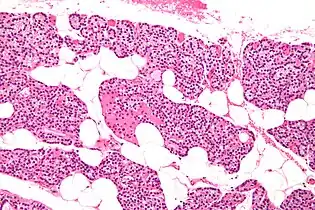

The parathyroid glands are named for their proximity to the thyroid—and serve a completely different role than the thyroid gland. The parathyroid glands are quite easily recognizable from the thyroid as they have densely packed cells, in contrast with the follicular structure of the thyroid.[6] Two unique types of cells are present in the parathyroid gland:

- Chief cells, which synthesize and release parathyroid hormone. These cells are small, and appear dark when loaded with parathyroid hormone, and clear when the hormone has been secreted, or in their resting state.[7]

- Oxyphil cells, which are lighter in appearance and increase in number with age,[7] have an unknown function.[8]

- Intermediate magnification micrograph. H&E stain. The white round structures are fat cells. Adipose tissue comprises 25–40% of normal parathyroid gland tissue.[7]